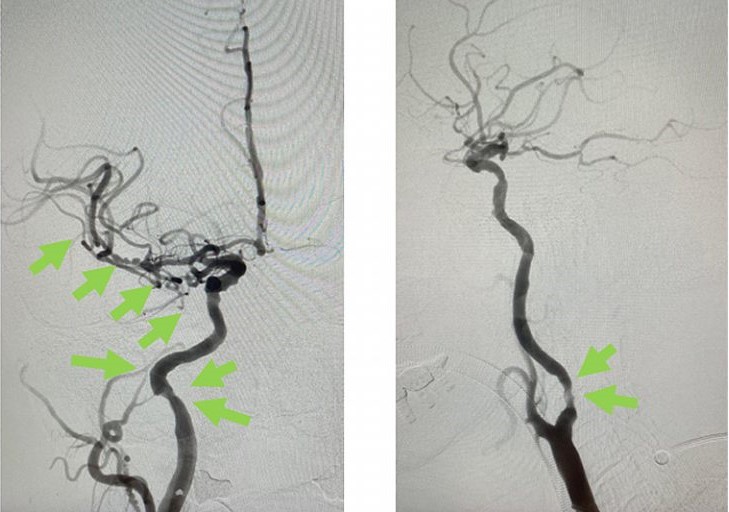

手術成功 患者手腳活動能力恢復

經過1小時的血管急救,所有血栓都被移除,羅先生的右頸和腦部血管都給順利打通,腦部缺血情況立即得到改善。血栓被吸取後,腦血管外科醫生發現羅先生的右頸內動脈有嚴重血管狹窄的情況,這個狹窄就是羅先生中風的主要原因。醫生因此植入血管支架來重新擴張狹窄的血管,以防止羅先生將來中風復發。全身麻醉清醒後,羅先生的大腦意識和手腳活動能力即時好轉,他其後再被送回另一間公立醫院繼續康復治療。